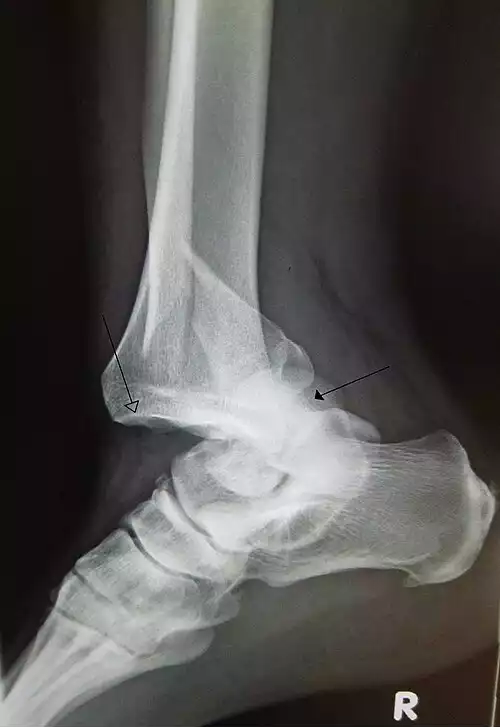

💡 یک گرافی اشعه ایکس در مواردی که سابقه تروما وجود دارد برای بررسی دررفتگی یا شکستگی مفید است. گرافی ممکن است علائم استئوآرتریت را نشان دهد.

دررفتگی ( به انگلیسی: luxation ) یک جابجایی دائمی در سطوح مفصلی نسبت به یکدیگر است. دررفتگی کامل در صورت از دست دادن ارتباط بین دو سطح مفصلی کامل است ولی هنگامی که قطع تماس مشتقات مفصلی جزئی باشد٬ دررفتگی نسبی ( subluxation ) نام می گیرد. در هنگام دررفتگی کامل٬ مفصل چنان پیچیده یا کشیده شده که استخوان ها از محل طبیعی خود در مفصل خارج یا جابه جا شده و ممکن است رباط ها نیز کشیده یا پاره شوند.

مهم ترین علامت در رفتگی بی حرکت ماندن سر استخوان در رفته در محل جدید بوده که همراه با کبودی و درد زیاد است.